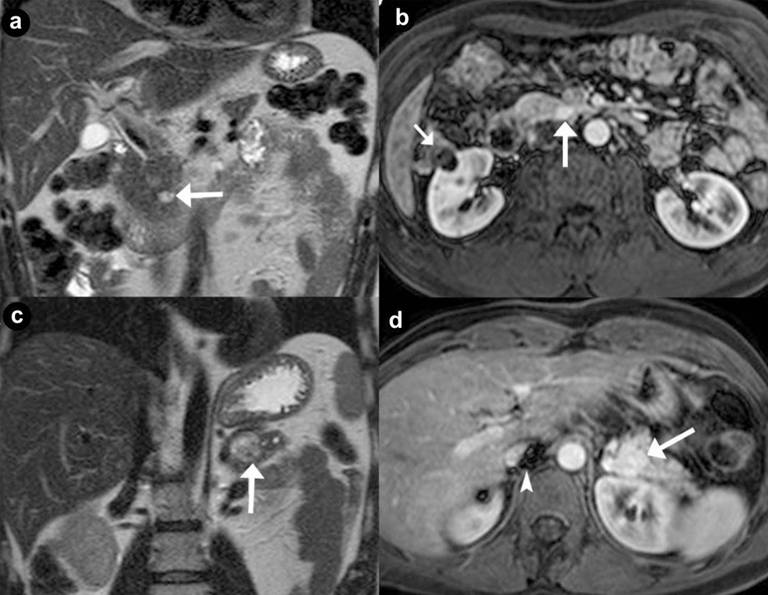

Figure 2. Pancreatic non functioning neuroendocrine tumors. Two cases suffering from VHL syndrome: a 39-year-old man (a. b.), and a 37-year-old man (c. d.). Coronal (a. c.) T2-weighted MR images; axial (b. d.) 3D volumetric gradient-echo T1-weighted fat suppressed images after intravenous contrast medium administration during arterial pancreatic phase of contrastographic dynamic study. In pancreatic head, a small, nodular solid lesion with maximum diameter of 12 mm (a. b. arrow), hyperintense on T2-weighted MR images, with homogeneous enhancement after intravenous contrast medium administration during arterial pancreatic phase is present. Main pancreatic duct is normal and common bile duct is not dilated. Small complex cystic mass in the right kidney without enhancement after intravenous contrast medium administration (b.) is present (short arrow). In pancreatic body-tail a solid, round mass with maximum diameter of 23 mm (c. d. arrow), heterogeneously hyperintense on T2-weighted MR images, with homogeneous enhancement after intravenous contrast medium administration during arterial pancreatic phase, is present. Artifacts are recognizable in the site of right adrenal gland (arrowhead), due to the presence of metallic staples of previous adrenalectomy for pheochromocytoma. |

Figure 3. Pancreatic non functioning neuroendocrine tumor and pancreatic serous cystadenoma in the same patient: asymptomatic 24-year-old man. Axial (a. b.) T2-weighted MR images, axial 3D volumetric gradient-echo T1-weighted fat suppressed images after intravenous contrast medium administration during arterial pancreatic (c. d.) and portal venous (e. f.) phases of contrastographic dynamic study. In pancreatic head a solid mass (a. arrow), heterogeneously hyperintense on T2-weighted MR images (a.) with homogeneous enhancement after intravenous contrast medium administration during arterial pancreatic phase of contrastographic dynamic study (c.), without wash-out in portal venous phase (e.) is present. In pancreatic head a cystic parenchymal lesion (short arrow), more hyperintense than solid mass, with fluid signal intensity on T2-weighted MR images (b.), without enhancement after intravenous contrast medium administration during arterial pancreatic (d.), and portal venous phases (f.), is visible. Inside the cystic lesion a septa is recognizable. Pancreaticoduodenectomy with Whipple procedure was performed. Histological specimen showed the presence of pancreatic macrocystic serous cystadenoma and non functioning neuroendocrine tumor of pancreatic head. |

Thirty-four pancreatic lesions were found in the 23 patients. In qualitative analysis, the MR imaging findings were: 6 (26.1%) unilocular fluid cystic lesions (Figure 1abc): 3 (13.0%) in pancreatic head, 3 (13.0%) in pancreatic body-tail; 11 (47.8%) serous micro- or micro/macro-cystic cystadenomas (Figures 1def, 4, and 5): 1 (4.3%) in pancreatic head, 2 (8.7%) in pancreatic body-tail (Figure 1), 8 (34.8%) diffuse (Figures 4 and 5); 8 (34.8%) neuroendocrine solid tumors: all of them non-functioning NET and hypervascular during arterial pancreatic phase of contrastographic dynamic study (Figures 2, 3, 4, and 5), 4 (17.4%) at pancreatic head (Figures 2ab; 3ace, and 4), 4 (17.4%) at pancreatic body-tail (Figures 2cd and 5); 1 (4.3%) cystic non-functioning NET, diffuse in all pancreatic gland (Figure 6); in 4 (17.4%) cases association of non-functioning NET and pancreatic cystic lesions (3 cases of association of non-functioning NET and serous cystadenoma (13.0%); 1 case of association of non-functioning NET and pancreatic simple cystic lesion (4.3%)) were present (Figures 4 and 5). Vascular invasion was not detected in any patients.

At MR images [15, 24, 25, 26, 28, 29, 30, 33] these tumors are oval or round lesions, with well-demarcated margins, hypointense on the T1-weighted images, and show higher signal intensity than normal pancreatic parenchyma on T2-weighted images, but they have no so high signal intensity as cysts (Figures 2ac, 3a, 4bc, and 5bc).

They show intense and early enhancement after gadolinium-chelates injection during MR dynamic study, resulting hyperintense masses at enhanced pancreatic phase of MR study (Figures 2bd, 3c, 4e, and 5d), with a reduced or moderate reduced or non reduced signal intensity in successive venous and delayed phases of dynamic study because of wash-out, or low wash-out, or no wash-out of gadolinium contrast medium, respectively.

Differently to literature, in our series non functioning NETs had not a preferential site in pancreatic gland, resulting localized in 17.4% of cases in the pancreatic head (Figures 2ab, 3, and 4) and 17.4% in pancreatic body-tail (Figures 2cd and 5).